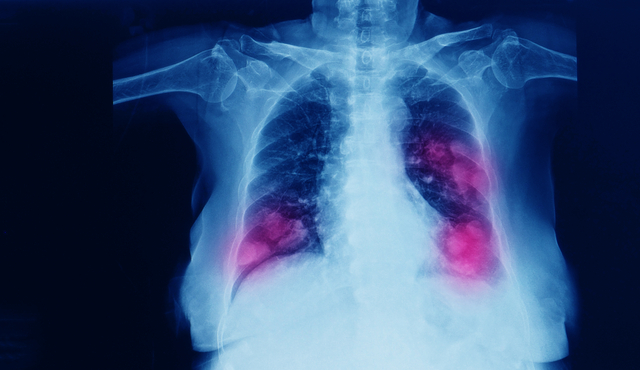

AKCİĞERLERDEN KALBE MİDEDEN SAÇLARA...

Sigara, tüm organlara ciddi derecede zarar verirken, özellikle akciğerler üzerinde ölümcül riskler oluşturabiliyor. Öyle ki akciğer kanserinin yüzde 90’ından sigara sorumlu oluyor. Prof. Dr. Bülent Tutluoğlu, sigaranın zararlarını şöyle sıraladı:

* KOAH, amfizem, astım, akciğer kanseri, akciğer kesecikleriyle ilgili hastalıklar